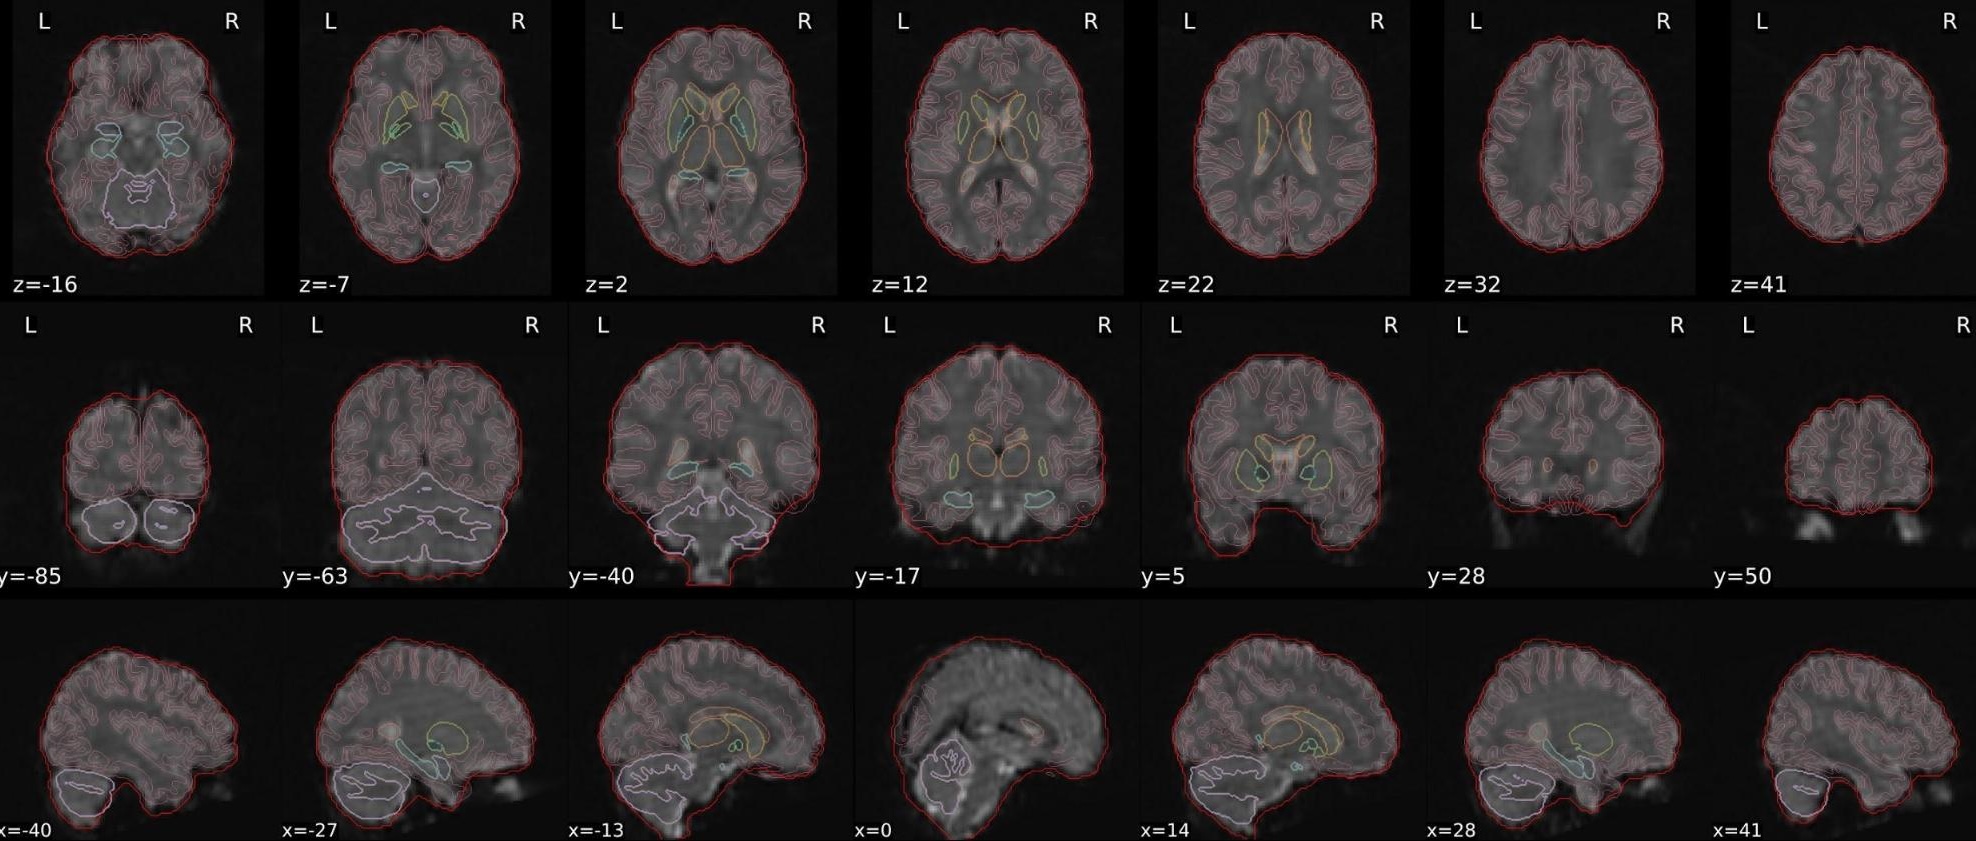

This QC step shows the registration of the T1 image to MNI space.

The registered T1 image is shown in the background with a brain atlas in MNI space as an overlay.

Example of a good subject

- If the registration performed well, you should see an overlap (i.e., correspondence of structures) between the MNI template and the T1 registered to the MNI space.

Example of a bad subject

- In case of poor registration, you should see a misalignment between the MNI template and the T1 (e.g., brain shifted down).

Summary

| good | bad |

|---|---|

| Structures of the MNI template and the registered T1 are well aligned | Structures of the MNI template and the registered T1 aren’t well aligned, e.g. brain is shifted downwards |